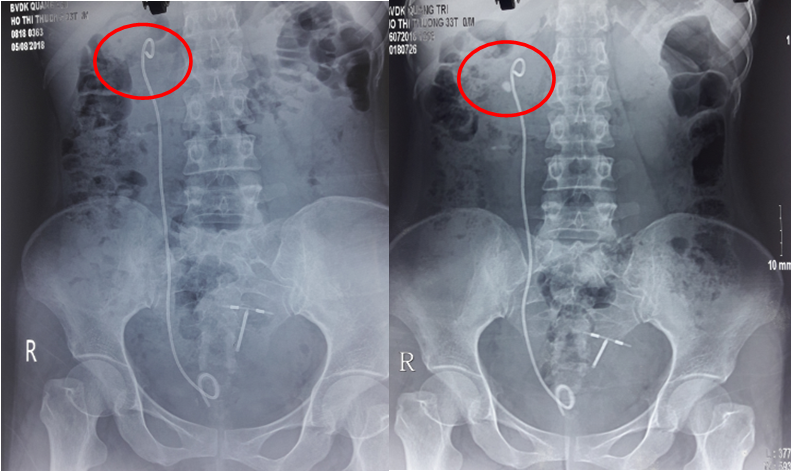

Hình 3.Hình ảnh sỏi thận trước tán và sau tán

Nếu nhiều hơn 2 mảnh sỏi nằm trên niệu quản và dẫn đến tắc nghẽn thận thì được gọi là chuỗi sỏi (steinstrasse). Thông thường 1 mảnh sỏi lớn sẽ gây tắc nghẽn niệu quản trước, sau đó những mảnh sỏi sau sẽ mắc kẹt ở phía trên.

10

Hình 10.Chuỗi sỏi niệu quản phải đoạn chậu sau TSNCT

ở bệnh nhân mang sỏi san hô được điều trị kết hợp TSNCT và LSTQD

Nguyên nhân dẫn đến chuỗi sỏi thường là do kích thước viên sỏi ban đầu lớn, vì vậy những viên sỏi > 2,5cm đều được khuyến cáo là không phù hợp với TSNCT.

Vị trí chuỗi sỏi thường gặp nhất là niệu quản đoạn xa (64%), kế đó là đoạn gần (29%) và cuối cùng là đoạn giữa (8%).